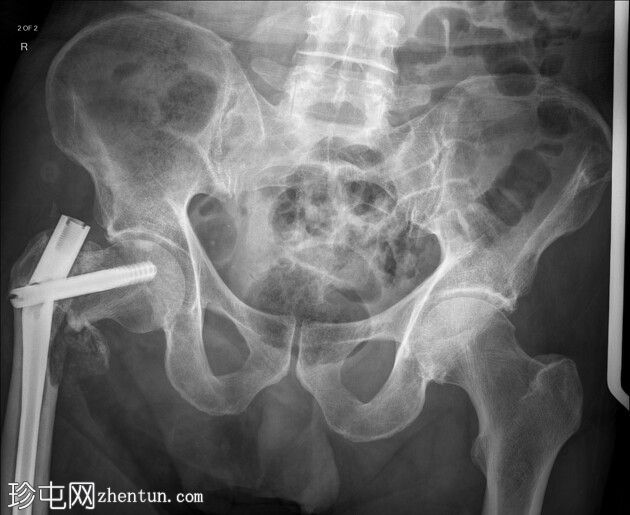

术中恢复期影像学检查:股骨髓内钉固定穿过小转子水平处已知的溶骨性病变。无金属部件损坏或假体周围骨折。